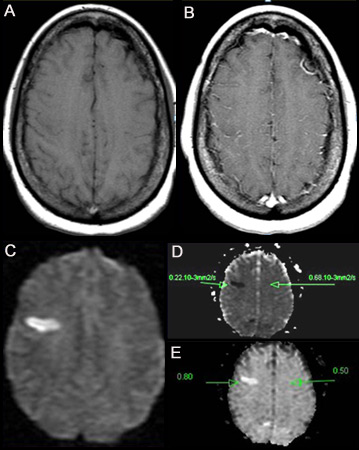

Ressonância magnética ponderada por difusão

Considere a ressonância magnética ponderada por difusão da cabeça com sequências específicas para AVC (IPD com imagem por susceptibilidade ponderada ou T2*) se o diagnóstico permanecer incerto apesar da TC de crânio.[64]

[Figure caption and citation for the preceding image starts]: (A) Imagem por ressonância magnética nuclear (RNM) ponderada em T1 sem contraste. (B) IRM ponderada em T1 pós-contraste mostrando aumento mínimo nos vasos leptomeníngeos sobre a região frontal direita. (C) Imagem ponderada por difusão (IPD) mostrando uma área hiperintensa na região frontal direita. (D) Mapa de coeficiente de difusão aparente (CDA) mostra lesão hipointensa, indicando difusão restrita que se correlaciona com uma alta intensidade na IPD e difusão exponencial. (E) O valor de ADC é 0.22 x 10³ mm²/segundo, correspondendo a um infarto hiperagudoDo acervo pessoal do Dr. Eric E. Smith; usado com permissão [Citation ends].